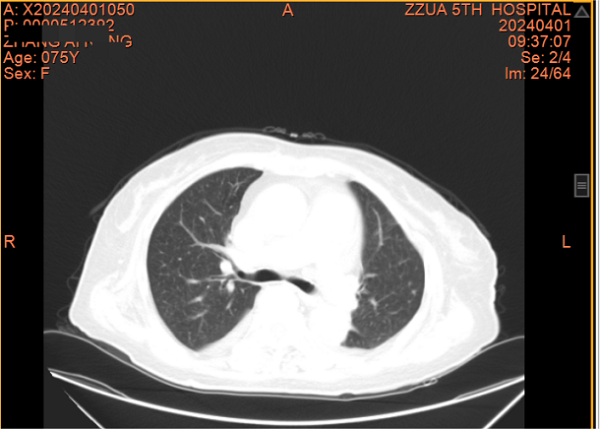

一个月前,张阿姨再发胸闷、心悸,这次张阿姨主动找到了全科医学科。住院期间因受凉出现鼻塞、流涕、发热,病情进展迅速,咳嗽、咳痰、胸闷、心悸、气喘等症状明显加重,动脉血气提示Ⅰ型呼吸衰竭并代谢性酸中毒。张阿姨精神特别差,情绪也十分低落。全科医学科主任刘培杰主任医师及别柏林主治医师综合分析病情后,第一时间给予碳青霉烯类积极抗感染、糖皮质激素抗炎、硝酸酯类扩张血管减轻心脏负荷、控制快速心室率、经鼻高流量湿化氧疗等综合治疗,护理团队给予饮食指导及心理辅导,张阿姨的病情很快得到控制,经复查胸部CT,肺部病变较前明显吸收,出院时再次对其慢性病管理及预防、治疗措施对其进行了再次的细致交代,病情好转出院。